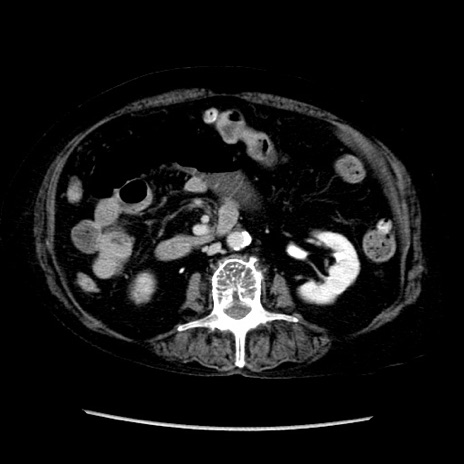

症例14(横断像)

【症例】 90歳代女性

【主訴】 腹痛・嘔吐

【現病歴】今朝から左側腹部痛を認めた。 経過観察していたが、嘔吐を認めたため来院。

【既往歴】 子宮癌術後

【身体所見】 意識清明、BP 127/54mmHg、P 98bpm Sp02 95%(RA)、BT 35.8°C、腹部平坦・軟腸ぜん動音聴取良好、右下腹部圧痛(+) 反跳痛なし

【データ】WBC 9800、CRP 0.46